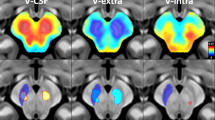

Partial correlation analyses were performed to investigate the correlation between LSV and MR estimates while controlling for intracranial volume (ICV). There was a significant positive correlation between MR estimates and LSV in the bilateral caudate and anterior and ventro-posterior putamen (Fig. 1). In addition, to exclude the existence of dopaminergic effects on MR estimates, correlation analysis was performed to uncover the correlation between DAT availability in the anterior putamen and MR estimate. In further analysis, we investigated whether there are between-group (tremor dominant type vs akinetic-rigid or mixed type) differences in the relationship between MR estimates and LSV using interaction analysis. The interaction term was not significant, which indicates that there was no group effect on the relationship between the MR estimate and the LSV.

Pearson’s correlation analyses showed that bilateral anterior and ventro-posterior putamen and bilateral caudate local volume significantly correlate with MR estimates. The mapped p values are the results after multiple comparisons correction using cluster-based statistics. Red represents the degree of significance of correlation coefficients.